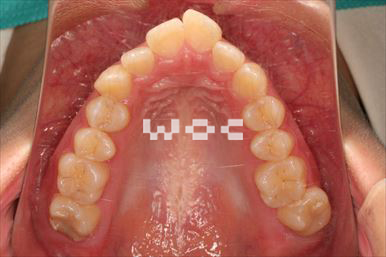

治療中1

出っ歯舌側矯正

上下舌側矯正を希望。

通院状況や歯みがきの協力が良かったため、1年7ヶ月で治療を終えることができました。※装置と注意事項に関しては、大人の矯正装置一覧へ。

- 年齢:20歳女性

- 主訴:出っ歯が気になる

- 基本矯正料金:120万円

- 治療期間:1年7ヶ月

- 抜歯部位:上顎両側第一小臼歯